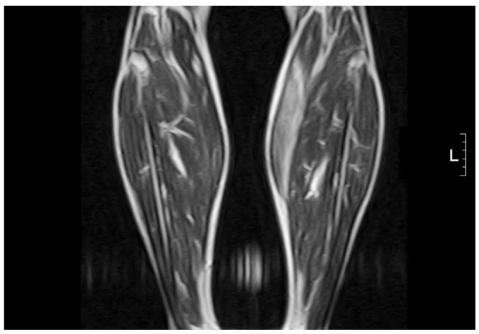

Myxoma is the most common primary tumor in the heart. Cardiac myxomas can present in various manners including embolization and fever, sometimes simulating endocarditis. However, they are rarely infected. We report here a case of an infected left atrial myxoma that seeded a normal mitral valve and atypically presented with multiple embolic events in the lower extremities along with multiple splenic and a cerebellar infarction.

黏液瘤是心脏最常见的原发性肿瘤。心脏黏液瘤可表现为多种形式,包括栓塞和发热,有时类似于感染性心内膜炎。然而,它们很少被感染。我们在此报告一例感染性左心房黏液瘤的病例,该肿瘤播散至正常二尖瓣,并以下肢多发栓塞事件以及多发脾脏和小脑梗死为特征,表现不典型。